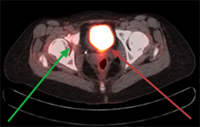

Benign brain tumor (memingioma, green arrows) compressing and affecting optic nerve (visual nerve, red arrow).

Highly focused stereostatic radiotherapy plan, treating the benign brain tumor (meningioma, green arrows) to high dose while sparing the normal brain, eyes and optic nerves.